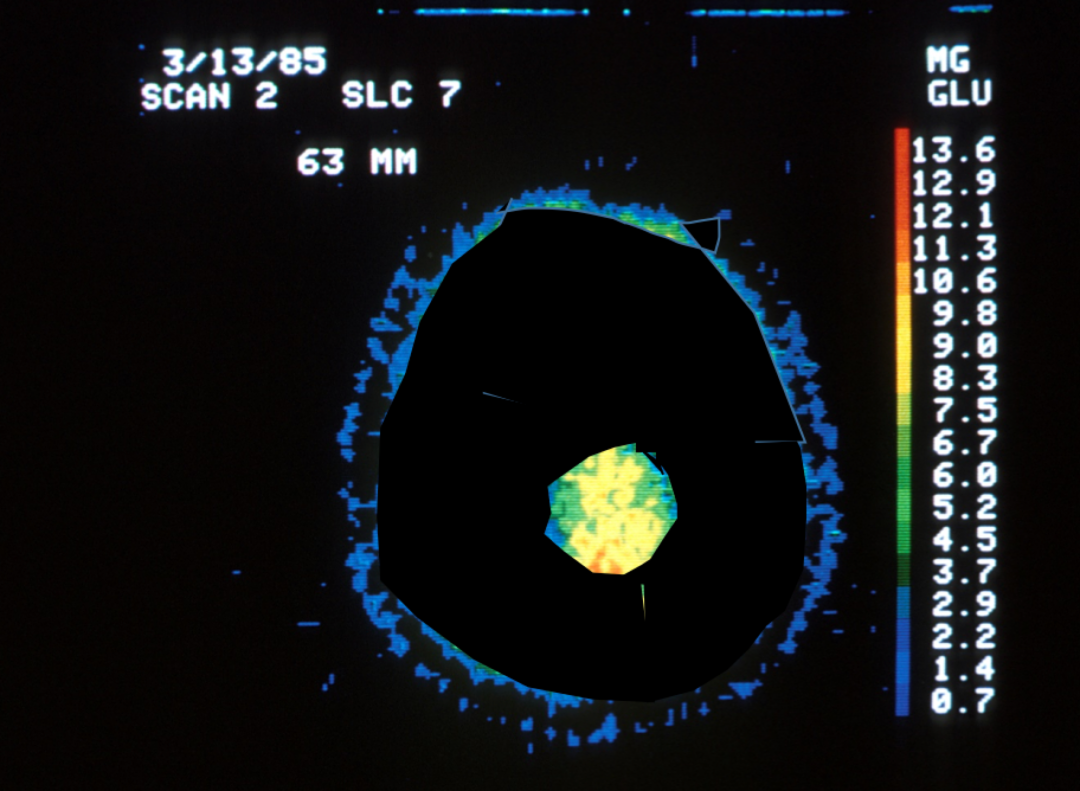

如果我们只使用10%的大脑,那么PET扫描应该看起来是这样:

图片

(中间亮光区域为活跃的大脑结构,不活动区域均为黑色)